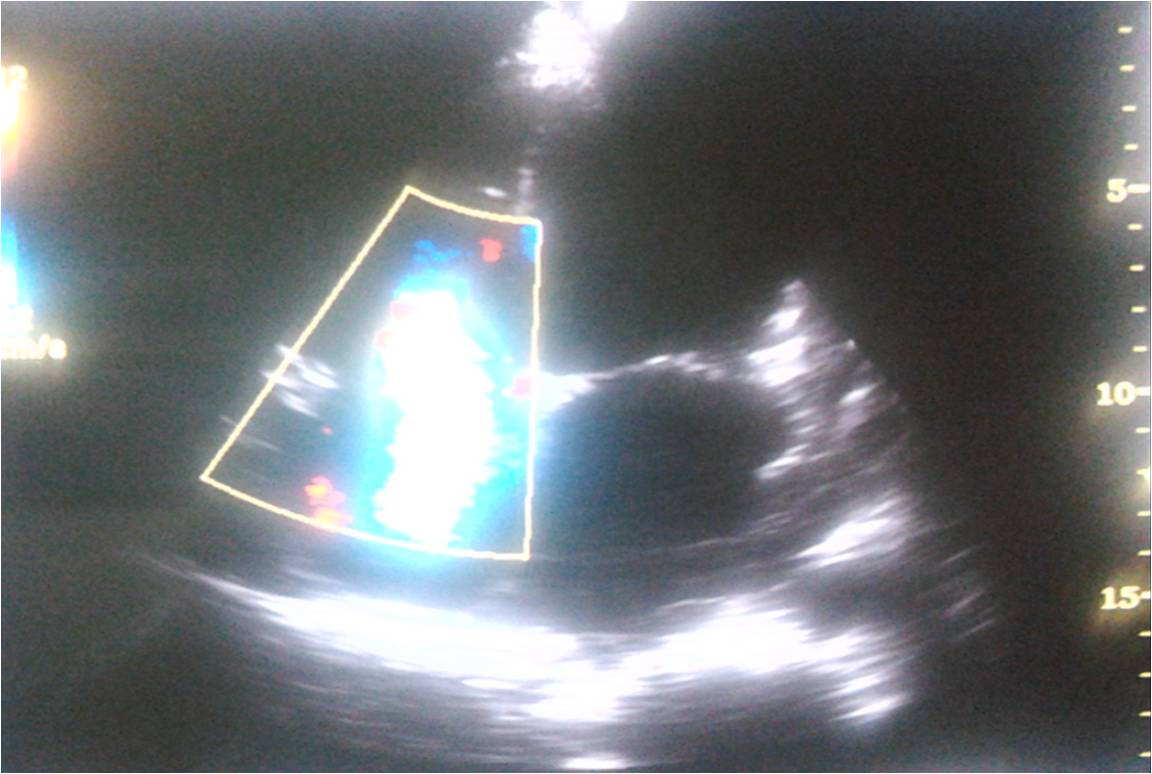

Moderate TR due to dilatation of tricuspid annulus.This patient had dilatation of all 4 chambers of the heart.LV EF was 24 %

And  now  , we have observed a new echocardiographic  sign   ie  TR jet alternans  in patient with  DCM .

Note the changing TR velocity implying severe RV contractile dysfunction.